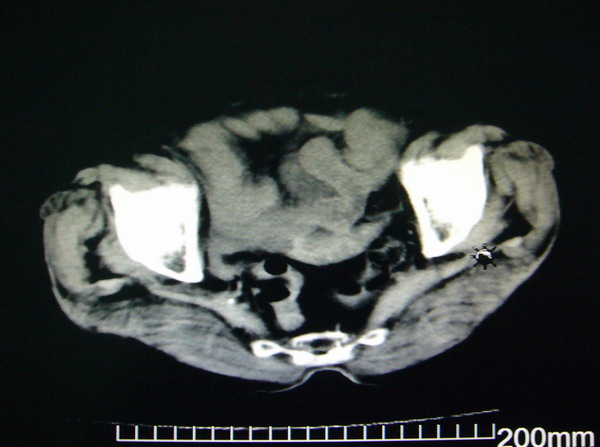

女:83y,转移性右下腹痛2小时,白细胞计数增高。

1.右侧肾盂扩大,肾盏无扩张,考虑:先天性肾盂变异可能性大。

2.胆囊扩张,考虑:胆囊炎。

3.阑尾区域可见以结节样高密度影,结合病史,考虑:阑尾结石,阑尾炎。

右下腹肠系膜增厚,结合病史支持阑尾炎.

右侧壶腹型肾盂可能,建议输路造影或增强

1.右侧肾盂扩大,考虑先天性肾盂变异或肾盂旁囊肿。

2.胆囊扩张,考虑胆囊炎。

3.阑尾区域可见结节样高密度影,结合病史考虑:阑尾结石、阑尾炎。